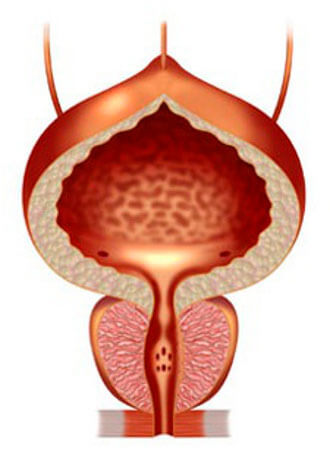

Prostatitis normal

Adenoma prostática

Si no curar la prostatitis, se desarrolla muy rápido y siempre lleva a la adenoma de la próstata ("la muerte masculina")